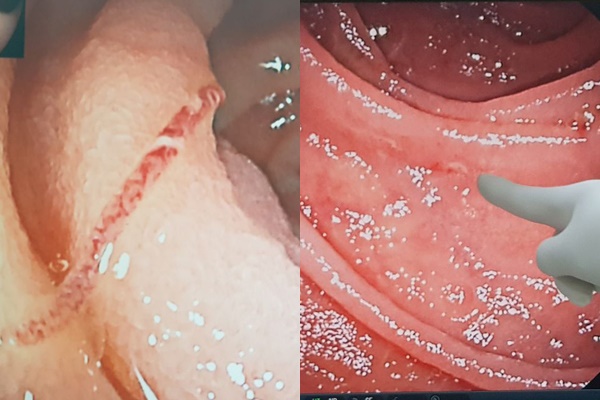

Hình ảnh giun mỏ bám hút máu trên thành ruột bệnh nhân (trái) và hình ảnh các tổn thương gây chảy máu

Kết quả nội soi bóng đôi phát hiện có nhiều giun lúc nhúc bám trên niêm mạc ruột, đám giun đang hút máu gây nhiều điểm tổn thương trên ruột, gây chảy máu.

Các bác sĩ đã gắp giun và sinh thiết tổn thương cho bệnh nhân, trong đó có vị trí ruột non lúc nhúc gần 20 con giun trưởng thành đang bám.